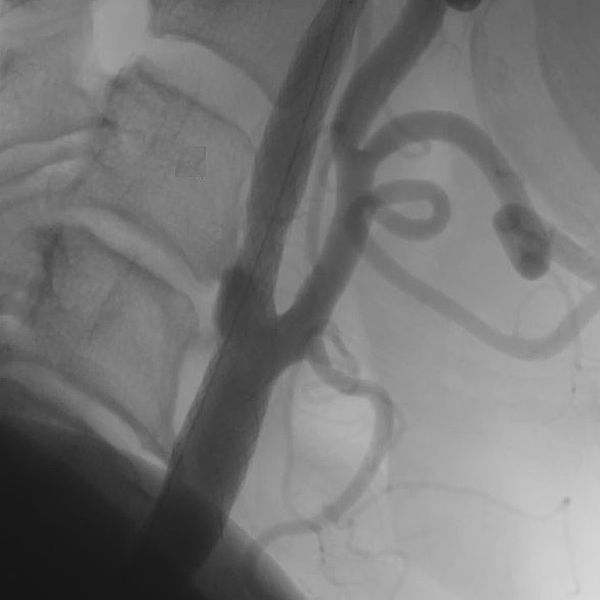

Die interventionelle Therapie von Stenosen erfolgt über einen Gefäßkatheter, der meist von der Leiste oder vom Arm bis in den Halsbereich vorgeschoben wird. Dort kann mit Hilfe eines Ballons die Engstelle zunächst aufgedehnt und dann mit einer Gefäßstütze (Stent) stabilisiert werden.